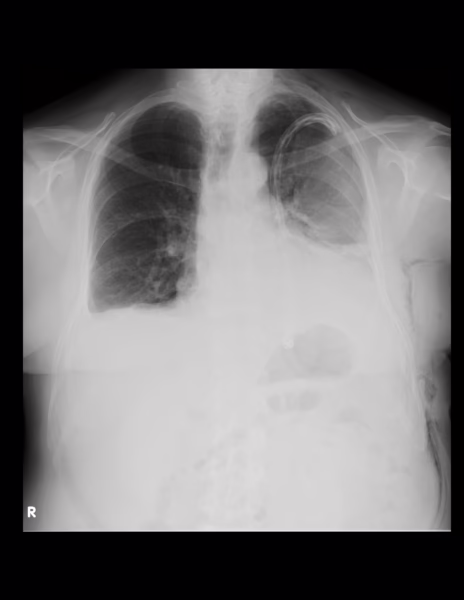

Opacidad en el hemitórax izquierdo haciendo signo de silueta con el contorno cardiaco, identificamos broncograma aéreo en la región parahiliar, obliteración del ángulo costodiafragmático lo que sugiere engrosamiento y/o derrame pleural, sonda torácica proyectada en el hemitórax izquierdo cuya punta se localiza en la porción superior.

IMPRESIÓN DIAGNOSTICA:

Enfisema subcutáneo en los tejidos blandos a la porción lateral izquierda del cuello, tórax y abdomen.

Opacidad en el hemitórax izquierdo haciendo signo de silueta con el contorno cardiaco, el mediastino se observa central lo que sugiere doble componente de derrame y atelectasia, identificamos broncograma aéreo en la región parahiliar, obliteración del ángulo costodiafragmático lo que sugiere engrosamiento y/o derrame pleural, sonda torácica proyectada en el hemitórax izquierdo cuya punta se localiza en la porción superior.

Obliteración de los ángulos cardiofrénico y costodiafragmático del hemitórax derecho con infiltrado intersticial basal con tendencia a la consolidación con imágenes lineales radiolúcidas que sugieren broncograma aéreo.